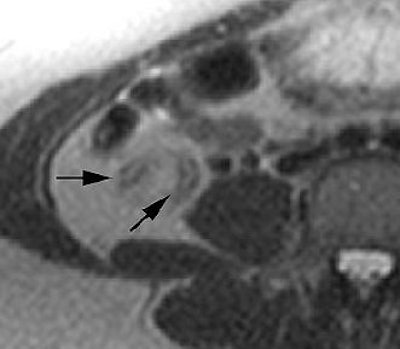

| Mild acute appendicitis in a 27-year-old pregnant woman (gestational age, 13 weeks). Above, transverse and, below, sagittal T2-weighted half-Fourier single-shot fast SE images (1076/60, 4-mm-thick sections, 192 x 256 matrix, 130° flip angle, 62-kHz bandwidth, 35-cm FOV) show an enlarged fluid-filled appendix measuring 7 mm in diameter (arrows). Note the increased signal intensity in the mesoappendix, a finding that is consistent with inflammatory changes (arrowheads). The MR images were interpreted as positive for acute appendicitis. Mild acute appendicitis was confirmed at surgery and pathologic examination. |